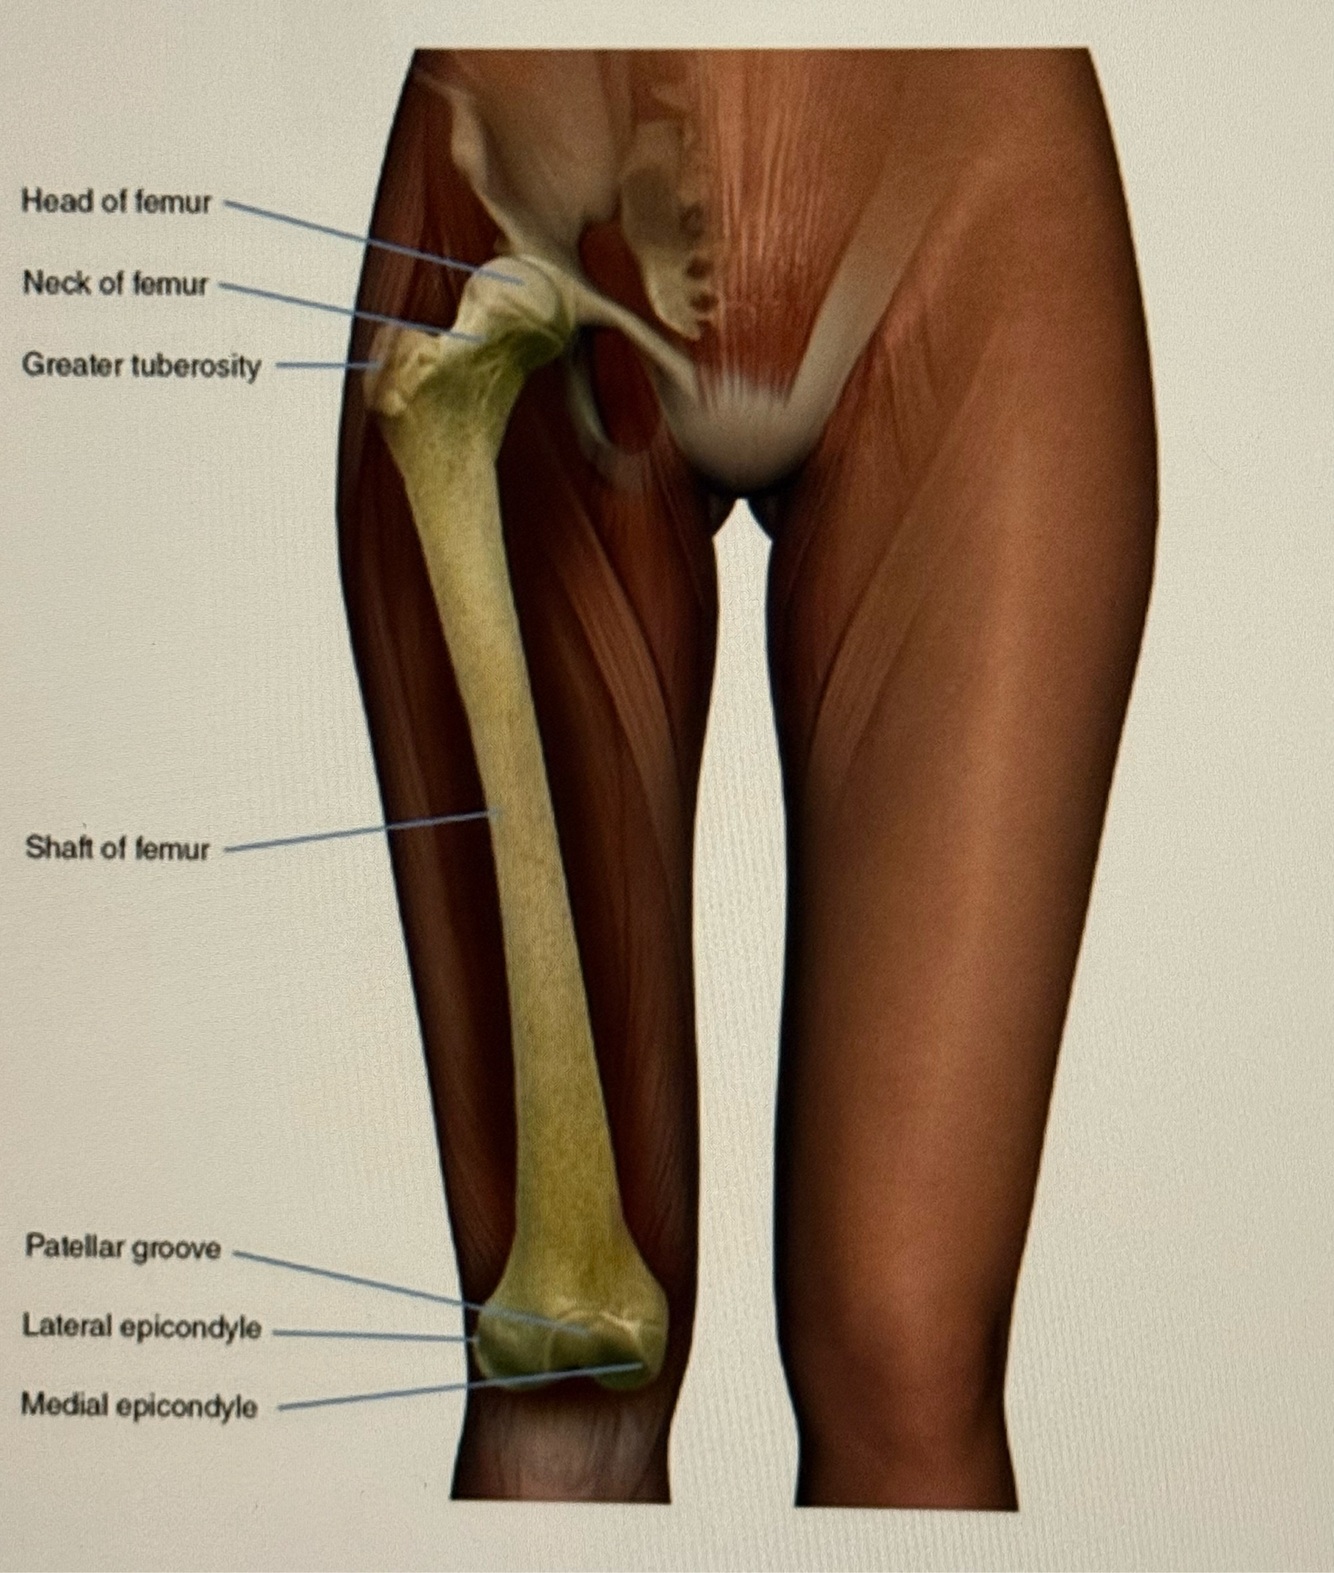

Letter A points to the

A

Acetabulum

Q

Letter B points to the

Labrum

9

Letter C points to the

Femoral neck

10

Letter D points to the

Obturator externus

11

Letter E points to the

Adductor muscles

12

Letter F points to the

Vastus lateralis

13

Letter G points to the

Femur

14

Letter H is pointing to the

Greater trochanter

15

Letter J points to the

Femoral head

16

Letter K points to the

Body of the ilium

17

Letter L points to the